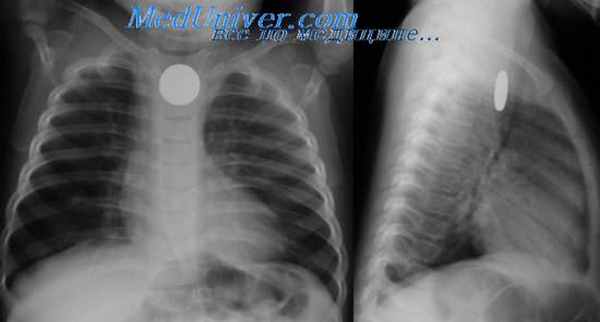

Эзофагография при атрезии пищевода

Далее обязательно проводится рентгенологическое обследование для подтверждения диагноза. На обзорном снимке грудной и брюшной полостей начало зонда определяется в слепом конце пищевода, далее наличие газа в желудочно-кишечном тракте позволяет дифференцировать свищевые формы атрезии пищевода. Отсутствие газа в желудке при обзорной рентгенографии чаще всего связано с отсутствием сочетания атрезии пищевода со свищем в трахею.

Подозрение на атрезию пищевода возникает при невозможности провести назогастральный зонд. Отсутствие газа в желудочно-кишечном тракте на рентгенограмме подтверждает диагноз атрезии пищевода без трахеопищеводного свища. Контрастное рентгенологическое исследование в большинстве случаев помогает оцепить длину проксимального отрезка пищевода. У большинства детей она невелика и расстояние между слепыми концами отрезков значительно (атрезия с большим диастазом).